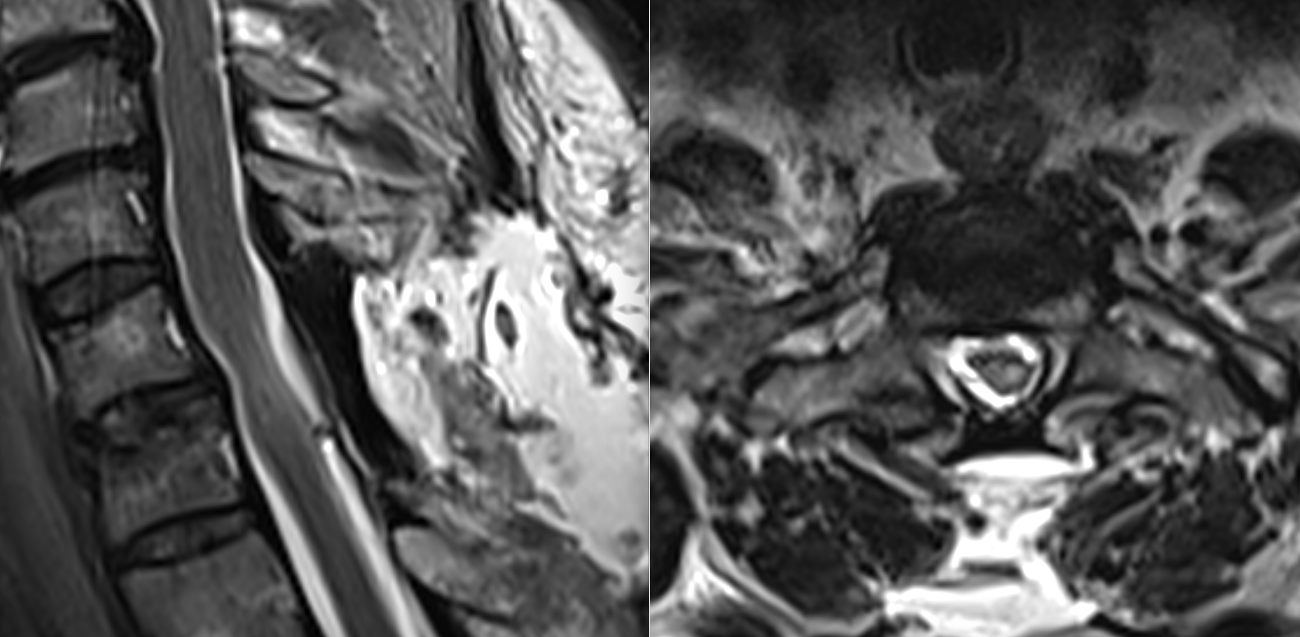

RMN-ul de control postoperator a evidențiat rezecția completă a formațiunii tumorale.

Măduva apare decomprimată, reexpansionată, cu refacerea spațiului lichidian perimedular — un indicator imagistic esențial al succesului chirurgical.

Dar dincolo de imagine, contează evoluția pacientului. Postoperator, deficitul motor nu s-a agravat, iar în perioada precoce s-au observat primele semne de recuperare:

o forță ușor crescută, un control mai bun al mișcărilor fine.